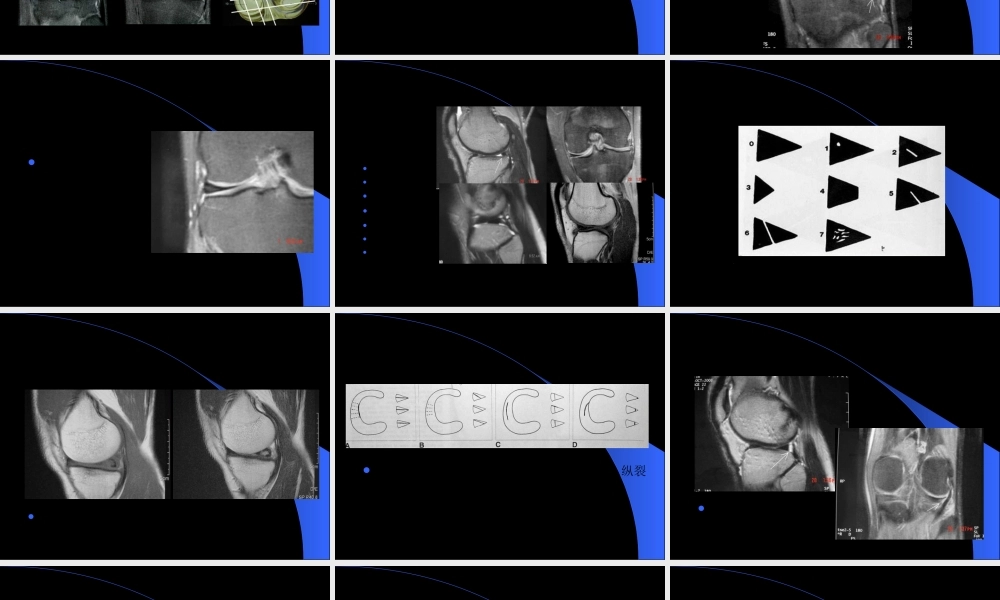

MRIMRI在膝关节创伤在膝关节创伤(chuāngshāng)(chuāngshāng)的应用的应用第一页,共五十一页。膝关节创伤的MRI半月板病变(bìngbiàn)韧带病变软骨病变其它第二页,共五十一页。半月板-解剖纤维软骨结构LM:类圆形(O),前后部分相对等宽–外周疏松连接,外后腘肌腱和鞘与关节囊分开–半月板股骨韧带MM:半圆形(C),后部(hòubù)比前部宽–外周与关节囊紧密连接10MM3LM2ACL8PCL第三页,共五十一页。半月板-技术考虑矢状位和冠状位短TE图像(túxiànɡ)优于长TE图像(túxiànɡ)-T1WI,PDWI,GRE优于T2WI第四页,共五十一页。正常半月板断层表现第五页,共五十一页。半月板撕裂诊断标准信号异常:Grade0:纤维软骨结构,所有(suǒyǒu)序列上低信号Grade2:变性Grade3:半月板撕裂第六页,共五十一页。半月板撕裂-Grade3信号第七页,共五十一页。半月板-Grade2信号可以演变(yǎnbiàn)为撕裂第八页,共五十一页。半月板撕裂-形态异常游离(yóulí)缘变钝小的三角形破碎消失领结中断局限性凹陷后角小于前角外侧半月板前角高度>6mm第九页,共五十一页。半月板撕裂诊断标准同时(tóngshí)考虑信号和形态的改变第十页,共五十一页。半月板特殊信号异常半月板内撕裂(sīliè)或囊肿第十一页,共五十一页。半月板撕裂分类层裂斜裂纵裂(zònɡliè)放射状撕裂注:MR的作用在于(zàiyú)明确有无撕裂,对撕裂的分型能力相对较差第十二页,共五十一页。见于(jiànyú)外侧半月板后角第十三页,共五十一页。半月板撕裂误诊可能-横韧带第十四页,共五十一页。第十五页,共五十一页。桶炳状撕裂-BHT的定义纵向垂直撕裂(sīliè)或斜行撕裂(sīliè)时合并半月板碎块向关节中央区移位,形如桶柄状内侧多于外侧内移的碎块多位于髁间和/或关节前部第十六页,共五十一页。BHT征象-双PCL征双后交叉(jiāochā)韧带征第十七页,共五十一页。BHT征象-半月板翻转征半月板翻转征(Flippedmeniscussign):半月板前角高度≥6mm;或“双前角征”—两个前角,而后(érhòu)角变短或消失第十八页,共五十一页。BHT征象-碎块内移征碎块内移征:关节(guānjié)髁间区见条状或团状低信号半月板碎块影第十九页,共五十一页。半月板囊肿多见于LM前角,常和半月板层裂同时(tóngshí)存在第二十页,共五十一页。盘状半月板(Discoidmenisci)LM多见分型Watanabeclassification第二十一页,共五十一页。盘状半月板-...